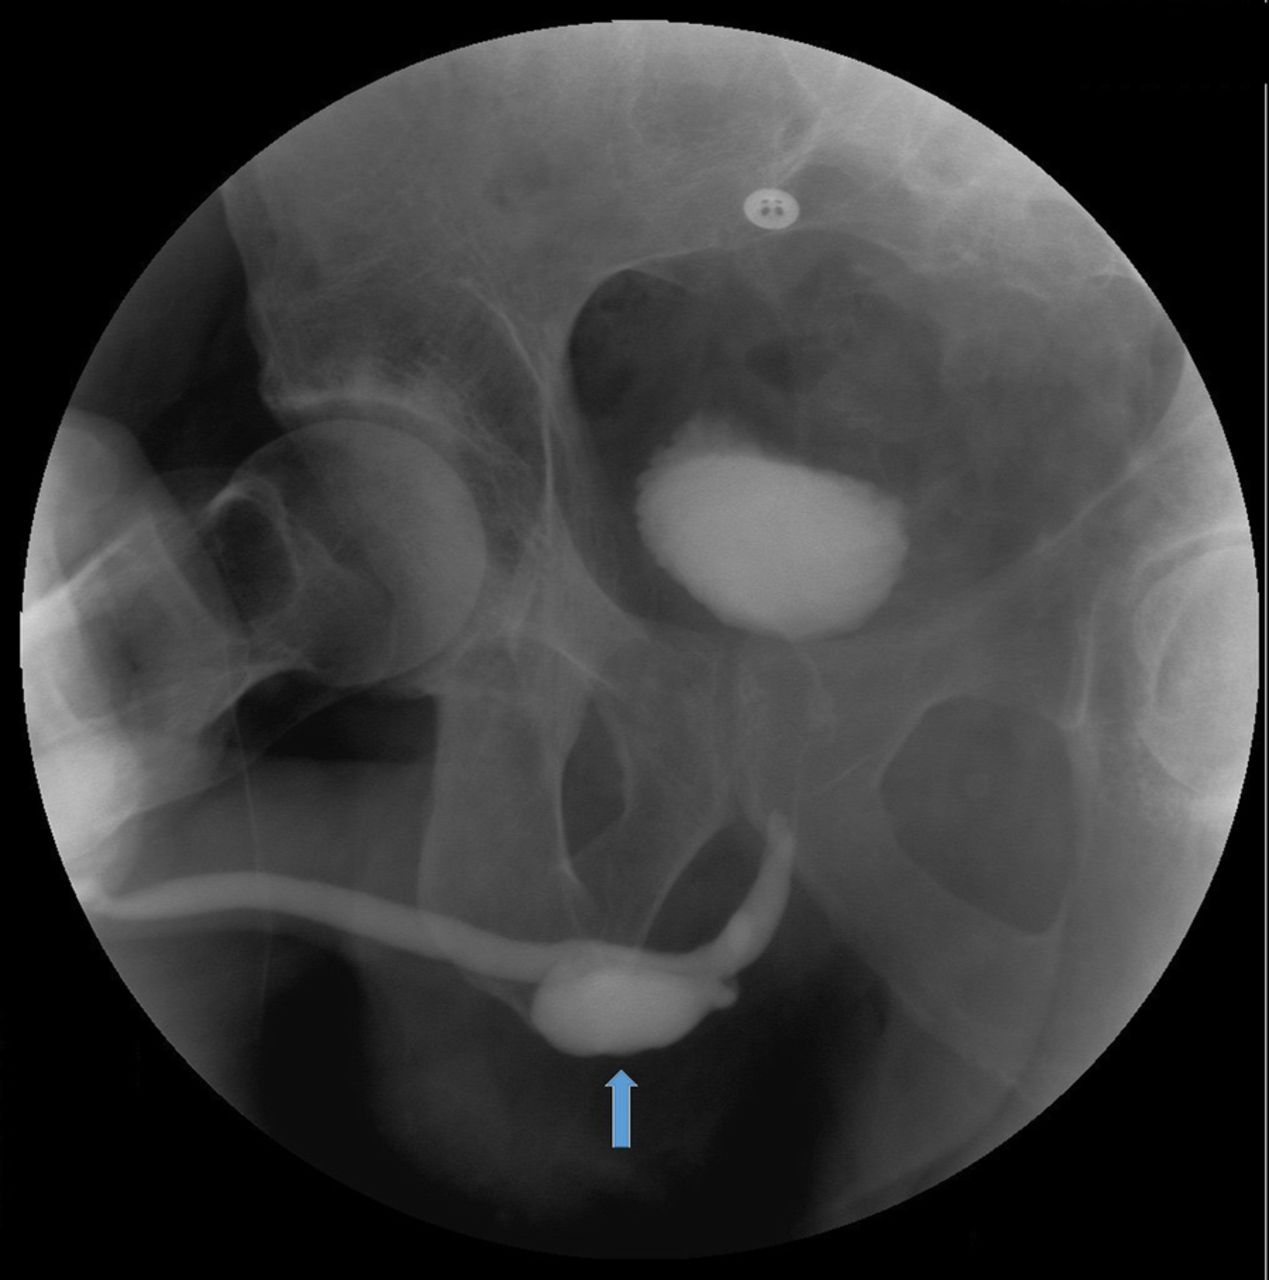

Learn about Mueller-Weiss syndrome, a rare degenerative condition affecting the navicular bone. Discover key symptoms, causes, and the latest treatment options, including orthotics, pain management, and surgical interventions. Understand how early diagnosis and expert podiatric care can help manage foot pain, improve mobility, and prevent long-term complications associated with this complex adult-onset foot disorder.

Read full article: Mueller Weiss Syndrome